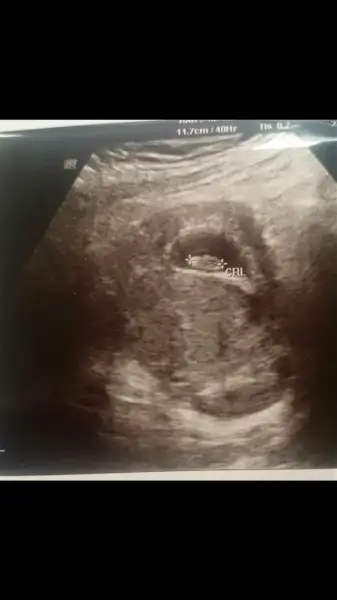

Cinsiyet nedir acaba 7+1 ama ultrasonda 6+4 çıktı

Kızlar 6+1 haftalık görüntü karından. Bana da tahminde bulunur musunuz

Çok erken ama merak ediyorum sağda gibi değil mi plesentası ilerki haftalarda tekrar danışırım insallah

Merhabaa biz de 7+6 yken böyleyiz teoriye göre tahmin yapar mısınız?karından usg

Kızlar buda benim 7 haftalık bugün kalp atışını da duyduk bide buna bakabilir misiniz sizce ne acaba